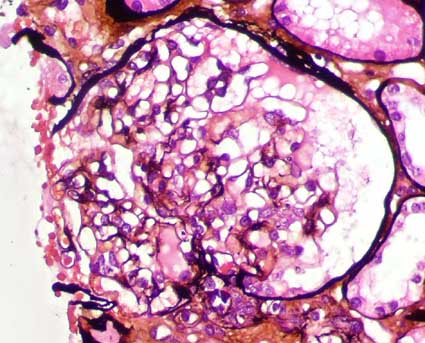

Figure 3.

PAS stain, X400.